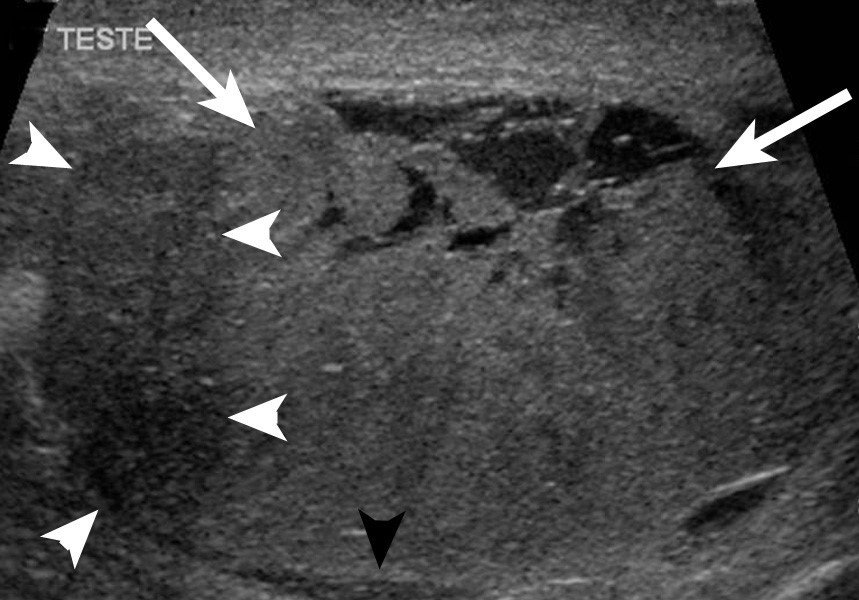

- УЗИ. Это исследование помогает определить присутствие или отсутствие опухоли почти со 100% точностью;